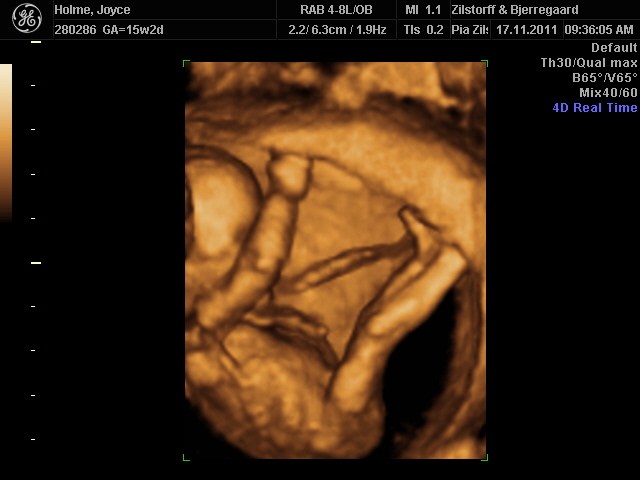

Vi fik at vide at ved en 3D så tidligt, er det mere en alien man får at se i stedet for en baby, og det havde vi ikke lyst til. Faktisk fik vi en alien at se ved alm 2D scanning og det syn kunne vi godt have undvære.

Hos Jordemoder.dk anbefalede de 3D omkring uge 28, da det er der man får de bedste billeder. Baby ligner en baby og der er stadig så meget plads i maven, at man får gode billeder.

Vi tog en 2D kønsscanning 15+0 og 3D/4D i 27+0 og det var hver en øre værd og mere til :-D